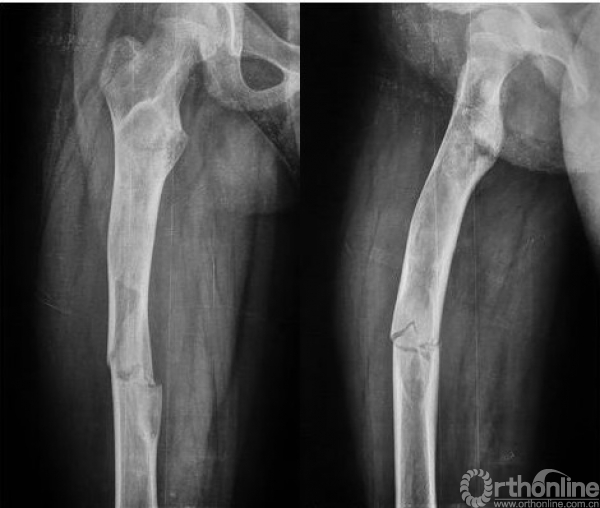

本病女性多见,男女发病率约为1.2:3,多在10岁左右发病,主要症状为轻微疼痛,局部肿胀及压痛。因症状轻微往往被忽略,多数病例是在以后查体或发生病理骨折时才被发现,骨折时疼痛可突然加重,肢体功能障碍,但骨折很少移位(图1),由于受累骨的坚固性受到明显影响,肢体可出现弯曲畸形,发生于股骨近端的常形成髋内翻,被称为“牧羊拐畸形”(图2)。

图1 股骨病理性骨折,没有明显的移位

图2 牧羊拐畸形